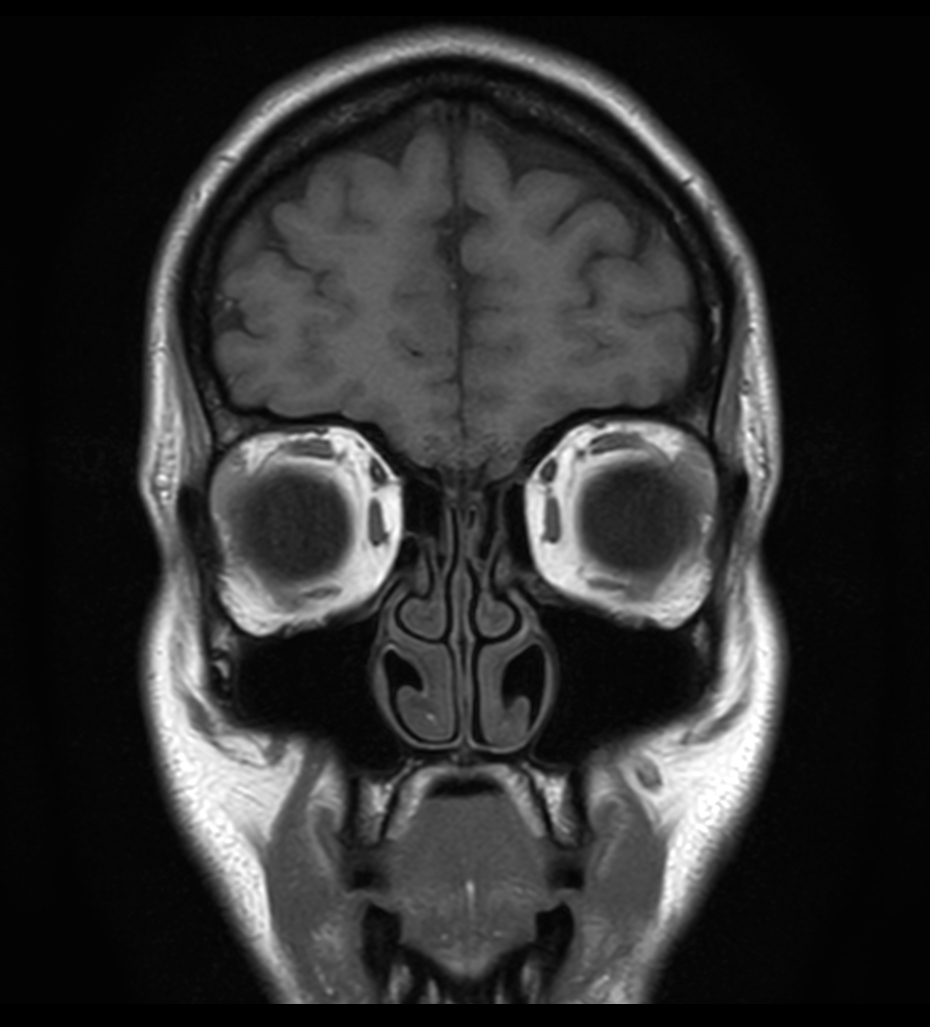

T1w TSE